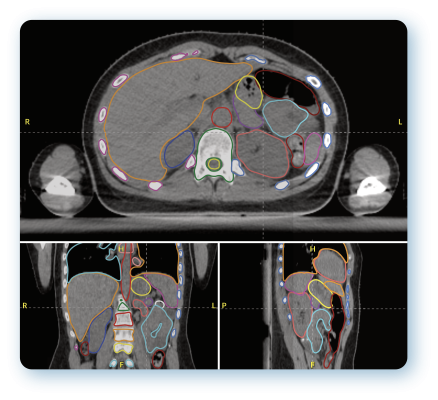

The partnership will commence with AutoContour, Radformation’s AI-driven contouring solution featuring 200 structure models, a robust toolset and image registration to accelerate the pre-treatment planning process, and RadMachine, a cloud-based platform used to streamline Machine QA to ensure the safety and optimal performance of treatment delivery systems, imaging technology, and ancillary equipment. This collaboration aims not only to enhance workflow efficiency and increase treatment accuracy but most importantly, to significantly improve patient outcomes.